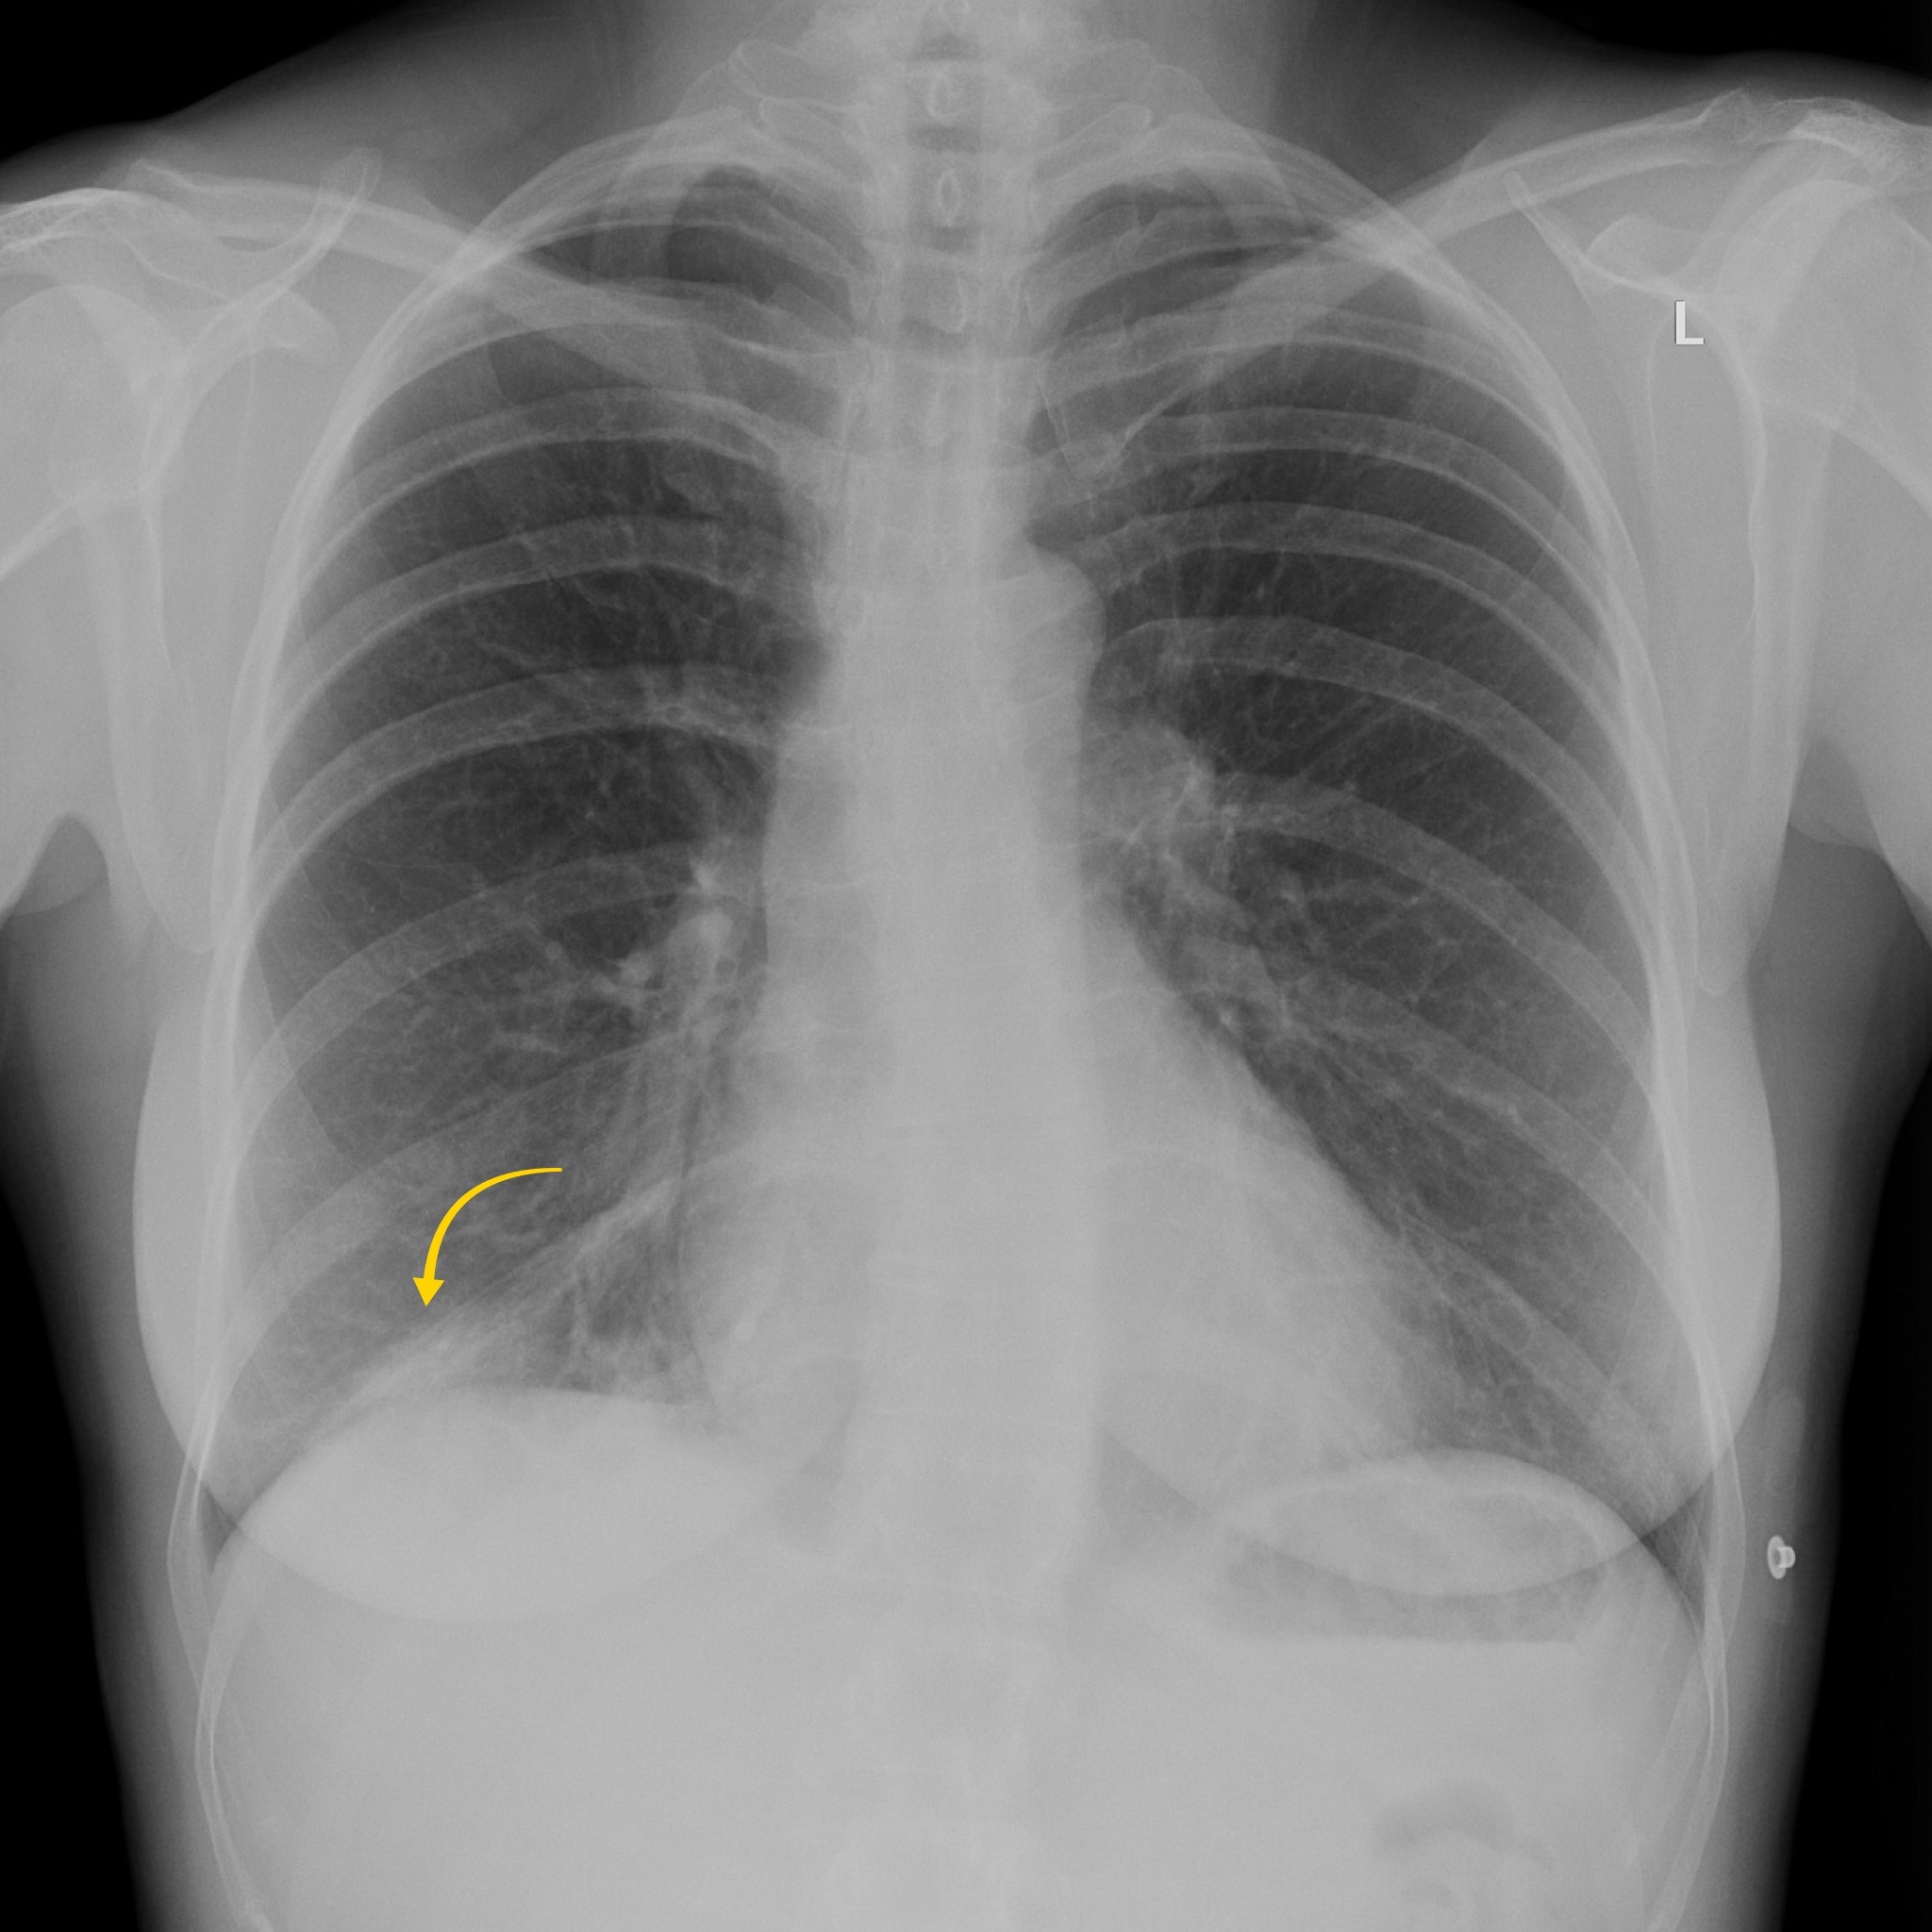

Although we couldn’t see this on our CT case, irregularity of the endplates can be seen after a few weeks on X-Ray and CT as well as loss of disc space. MRI is more sensitive and we are looking for high T2 or STIR signal within the endplates, disc and paraspinal tissues and psoas muscles. Gadolinium contrast can help as we may see enhancement of the endplates, disc and peripheral enhancement of any abscesses. It’s important on MRI to ensure there is no significant central canal stenosis secondary to abscess formation or vertebral collapse.